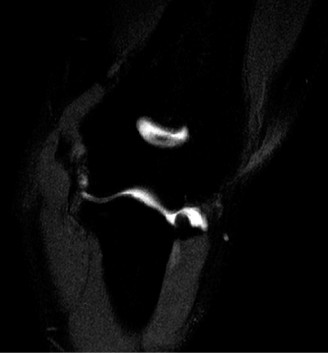

Identify the muscles that compose the force couples in the transverse and coronal planes? CASE 3 A 35-year-old male has had left shoulder pain for 4 months, ever since a low-speed motor vehicle accident (MVA). Physical examination demonstrates preserved range of motion but pain and some weakness with Jobe’s testing. His imaging is shown in Figure 2–8.

Figure 2–8_Reproduced with permission from Stadnick ME. _Partial Rotator Cuff Tears. MRI Web Clinic. 2007 (Apr).

What is the most likely diagnosis?

- Partial articular surface tendon avulsion (PASTA)

- Full-thickness rotator cuff tear

- Superior labrum anterior to posterior tear (SLAP)

- Anterior labral periosteal sleeve avulsion (ALPSA)

Discussion

The correct answer is (A). These are best diagnosed on an MRI as seen in the imaging provided; addition of intra-articular contrast can further improve this study. Answer B, full-thickness rotator cuff tear, is incorrect as the bursal side of the tendon can be seen to be in continuity. Answer C, a SLAP lesion, will be visualized as a labral tear on a coronal MRI and will be found at the biceps root. Answer D, an ALPSA lesion, will be most clearly seen on an axial MRI. It is a variant of a Bankart lesion where the labrum is displaced medially and inferiorly rolling down the glenoid neck underneath the periosteum.

Rotator cuff tears are a common reason for shoulder pain and a common reason to obtain shoulder imaging. As a result, numerous different imaging modalities exist offering different pros and cons. Plain films are still the initial imaging modality of choice. These are most useful in ruling out other possible diagnosis but can help with the diagnosis of a rotator cuff tear as well. Changes to the tendon itself

may appear as calcific tendinosis, which would most commonly be seen at the bone–tendon interface. A decrease in the acromiohumeral distance (less than 2 mm) may also be indicative of a cuff tear. In late cases of rotator cuff tears, superior subluxation of the humerus may be evident. Certain variations in acromial anatomy, including spurs or a hook-shaped (type 3) acromions, may be associated with rotator cuff tears as well. With progression of rotator cuff tears, degenerative changes including spurs, cysts, and sclerosis may be evident at the greater tuberosity. In late, massive tears one may see degenerative changes consistent with rotator cuff arthropathy.

Ultrasound has been gaining popularity recently as it is extremely cost effective when compared to MRI and allows a dynamic assessment of the tendons. It has been shown to have greater than 90% specificity and sensitivity when performed by an experienced operator.

MRI remains the most popular imaging modality for diagnosing rotator cuff tears. Normal rotator cuff tendon appears dark on both T1 and T2 sequences. Tears may be noted as being full-thickness, articular-sided, bursal-sided, or intrasubstance. They are visualized as a disruption in the regular contour of the tendon and increased signal intensity on T2 sequences. Occasionally, an MR arthrogram may provide additional information regarding a cuff tear, although this is not routinely ordered.